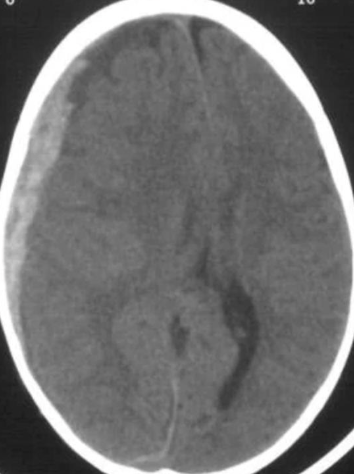

Epidural

“lucid interval”